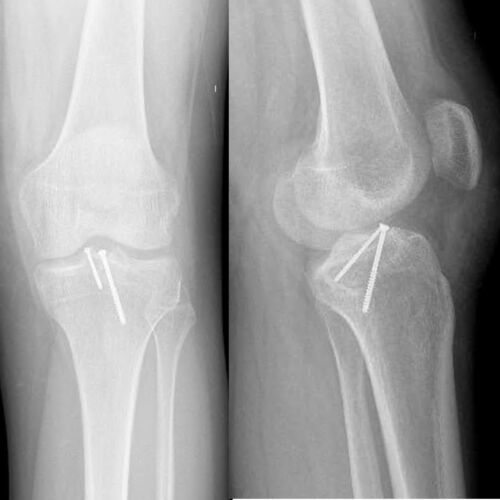

I was hit by car, had a compound fracture with a bone sticking out of my left foot. Broken tibia and fibia?. Screwed plate and bones back together. I am healing fine, next visit 3/26 to remove stiches. I seem to have total function of foot. Still have 2 more weeks of not using leg, but very hopeful.